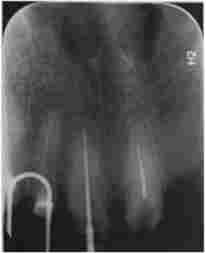

Візіограмма. Зуби 1.1, 1.2 і 2.1 під коронками. Пацієнт О., 67 років, готується до заміни коронок

Мал. 10.4. Візіограмма. Зуби 1.1, 1.2 і 2.1 під коронками. Пацієнт О., 67 років, готується до заміни коронок